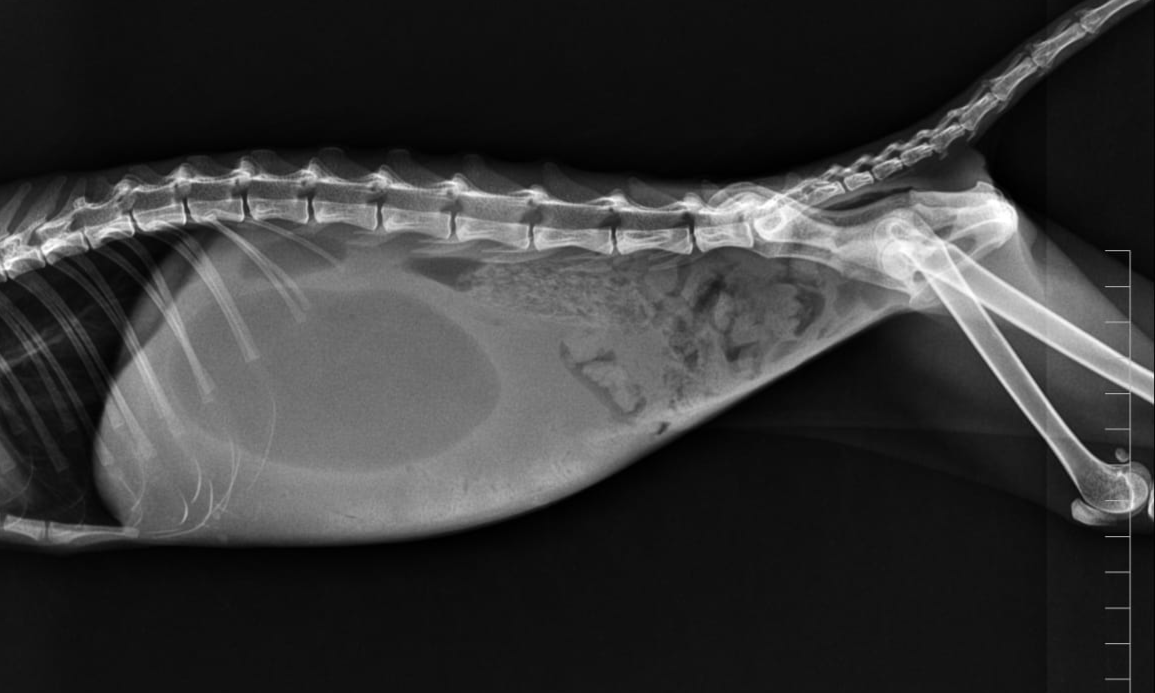

Abdominal radiographs revealed a markedly distended stomach filled with fluid and gas, with a distinct fluid–gas interface visible in the cranial abdomen

Fluid filled stomach due to duodenal obstruction causing improper emptying

Gastric distension due to fluid accumulation